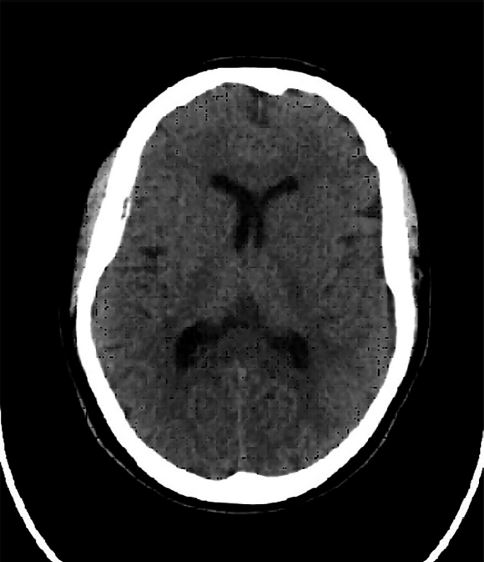

El 4 de enero del año 2024 se confirma el diagnóstico de EEO mediante la detección de anticuerpos IgM anti-EEOV (virus de encefalitis equina del Oeste) y genoma viral EEOV en LCR. El 16 de enero de 2024 se realiza traqueotomía y se da inicio al weaning respiratorio. Hacia el 2 de febrero de 2024, el paciente sigue sin mejoría del cuadro clínico, vigil, sin conexión con el entorno, polineuropático. Se repite la tomografía de cerebro (por encontrarse en desperfecto el resonador). Esta informa hipodensidad difusa de la sustancia blanca supratentorial y en focos más acentuados en la sustancia blanca córtico- subcortical a nivel de la convexidad cerebral, con hipodensidad difusa bilateral y simétrica de los núcleos grises de la base (Fig. 3). El paciente continúa traqueostomizado, con dificultad para el destete, ventilado con presión soporte/CPAP, sin requerimiento de inotrópicos, diuresis conservada por sonda, hemodinámicamente estable, vigil, apertura ocular espontánea, reflejo de succión como único reflejo arcaico, sin conexión con el medio que lo rodea, con estado de conciencia mínimo.

Figura 3. Tomografía del paciente luego de un mes y 7 días de evolución.